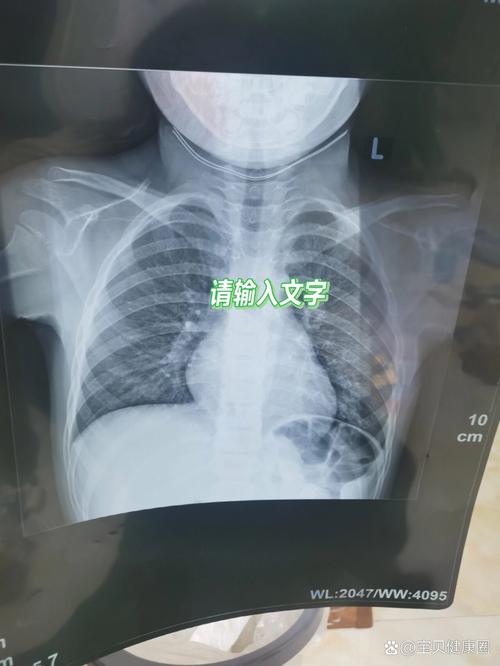

- “湿肺”现象(暂时性呼吸困难):胎儿在子宫内肺泡里充满了液体,出生时需要通过产道挤压和开始呼吸,将这些液体吸收并排出,这个过程有时会持续几天,导致宝宝呼吸时有“啰音”(类似痰响的声音),这是一种生理现象,会自行好转,但X光片可能显示类似肺炎的模糊影。

- 胸廓薄,透光性好:新生儿胸壁很薄,脂肪少,X光片上肺部纹理本身就比成人显得“多”和“模糊”,医生在解读时主观判断空间较大。

- 影像学不典型:新生儿肺炎的X光片表现常常不典型,不像大孩子那样有明显的“大片阴影”,可能只是肺纹理增粗、模糊,或有散在小片状影,这些表现既可能是肺炎,也可能是前面提到的“湿肺”或其他原因,不同的医生对同一张片的解读可能会有差异。